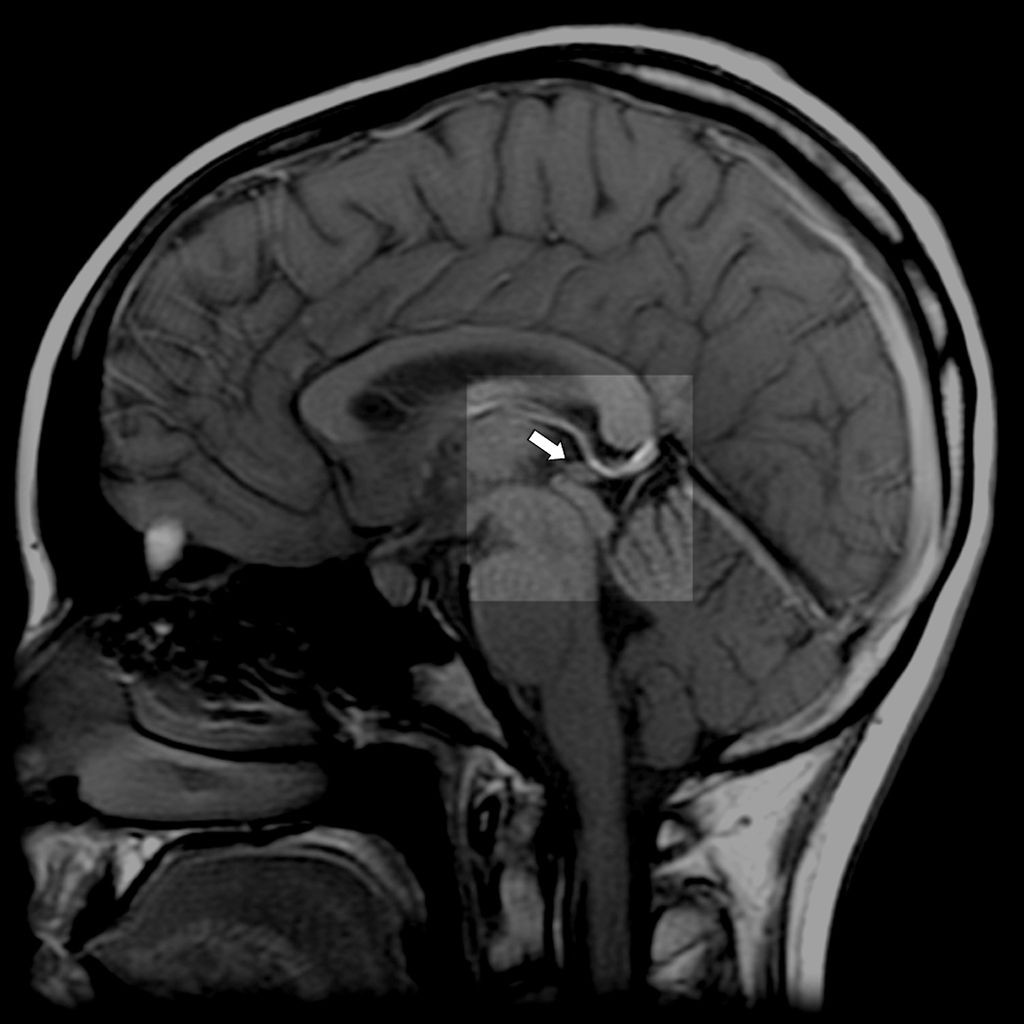

"La glándula pineal es nuestra radio"